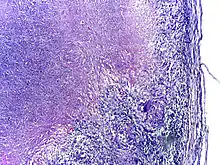

Tuberculosis is classified as one of the granulomatous inflammatory diseases. Macrophages, epithelioid cells, T lymphocytes, B lymphocytes, and fibroblasts aggregate to form granulomas, with lymphocytes surrounding the infected macrophages. When other macrophages attack the infected macrophage, they fuse together to form a giant multinucleated cell in the alveolar lumen. The granuloma may prevent dissemination of the mycobacteria and provide a local environment for interaction of cells of the immune system.[63] However, more recent evidence suggests that the bacteria use the granulomas to avoid destruction by the host's immune system. Macrophages and dendritic cells in the granulomas are unable to present antigen to lymphocytes; thus the immune response is suppressed.[64] Bacteria inside the granuloma can become dormant, resulting in latent infection. Another feature of the granulomas is the development of abnormal cell death (necrosis) in the center of tubercles. To the naked eye, this has the texture of soft, white cheese and is termed caseous necrosis.[63]